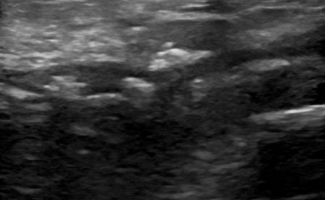

- Τενοντοπάθεια ή ρήξη γλουτιαίων τενόντων, ορθού μηριαίου και οπίσθιου μηριαίου

- Τροχαντηρίτιδα: συλλογή υγρού στους θυλάκους των γλουτιαίων τενόντων στο μείζονα τροχαντήρα